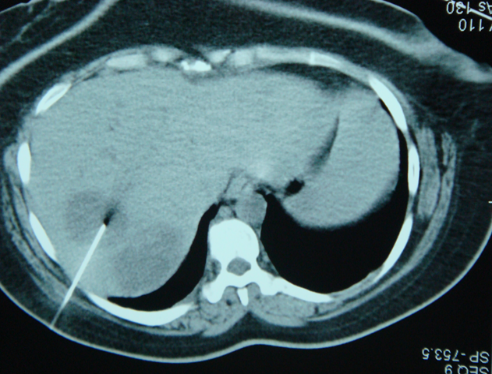

Abses diaqnozunu dəqiqləşdirmək üçün klinik əlmətlərlə yanaşı görüntüləmə və laborator müayinələr aparılmalıdır. Yerli və ümumi sepsis əlamətləri ilə yanaşı USM və ya tomoqrafiyada qaraciyərdə abses boşluğun görünməsi diaqnozu dəqiqləşdirir. Absesdə qaztörədən bakteriyalar olduqda və ya bağırsağa açılarsa içərisində qaz görünür (25%).

Diaqnostik əlamətləri:

• Ağrı, hepatomeqaliya, hərarət, septik əlamətləri

• Laborator septik əlamətlər

• Görüntüləmədə destruktiv ocaq